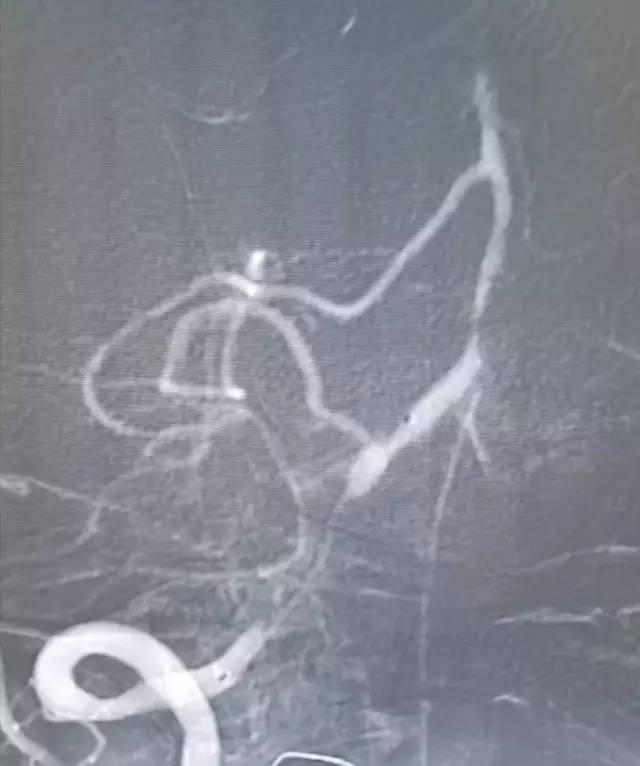

DSA:右侧椎动脉V4段重度狭窄,前向血流减慢,基底动脉近中段未见顺行显影,左侧椎动脉V4段远心端闭塞,右后交通动脉开放,经右颈内动脉造影可见基底动脉中远段显影,左胚胎型大脑后动脉(图3-5)。

图3

图4

图5